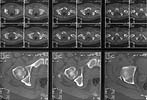

A male 25 y.o., admitted to us at 10th day after MVA. The hip luxation was reduced at the initial hospital acutely. The question is about his femoral head fracture (AP view and CT attached). How to manage this lesion? Leave "as is"? ORIF? The fragment removal?

As you may know, this is insufficient imaging provided for us to make treatment recommendations. No one would treat a patient with this type of unusual injury based on a single AP hip plain radiograph and a single axial image low through the joint.

Perhaps Judet obliques, and pelvic/acetabular zone CT scan images would reveal complete information to make a good plan.

I have left small fragments from the femoral head and patients seemed to do OK. This one appears to be relatively inferior and is not causing appreciable widening or malreduction of the hip joint.

I picked most clear views of the injury to my mind. At the moment available are one Judet view and, more CT scans and AP view of the pelvis where i cut the image from - attached to this and the next message. Quality of some initial films with luxation and after reduction is below than acceptable level.